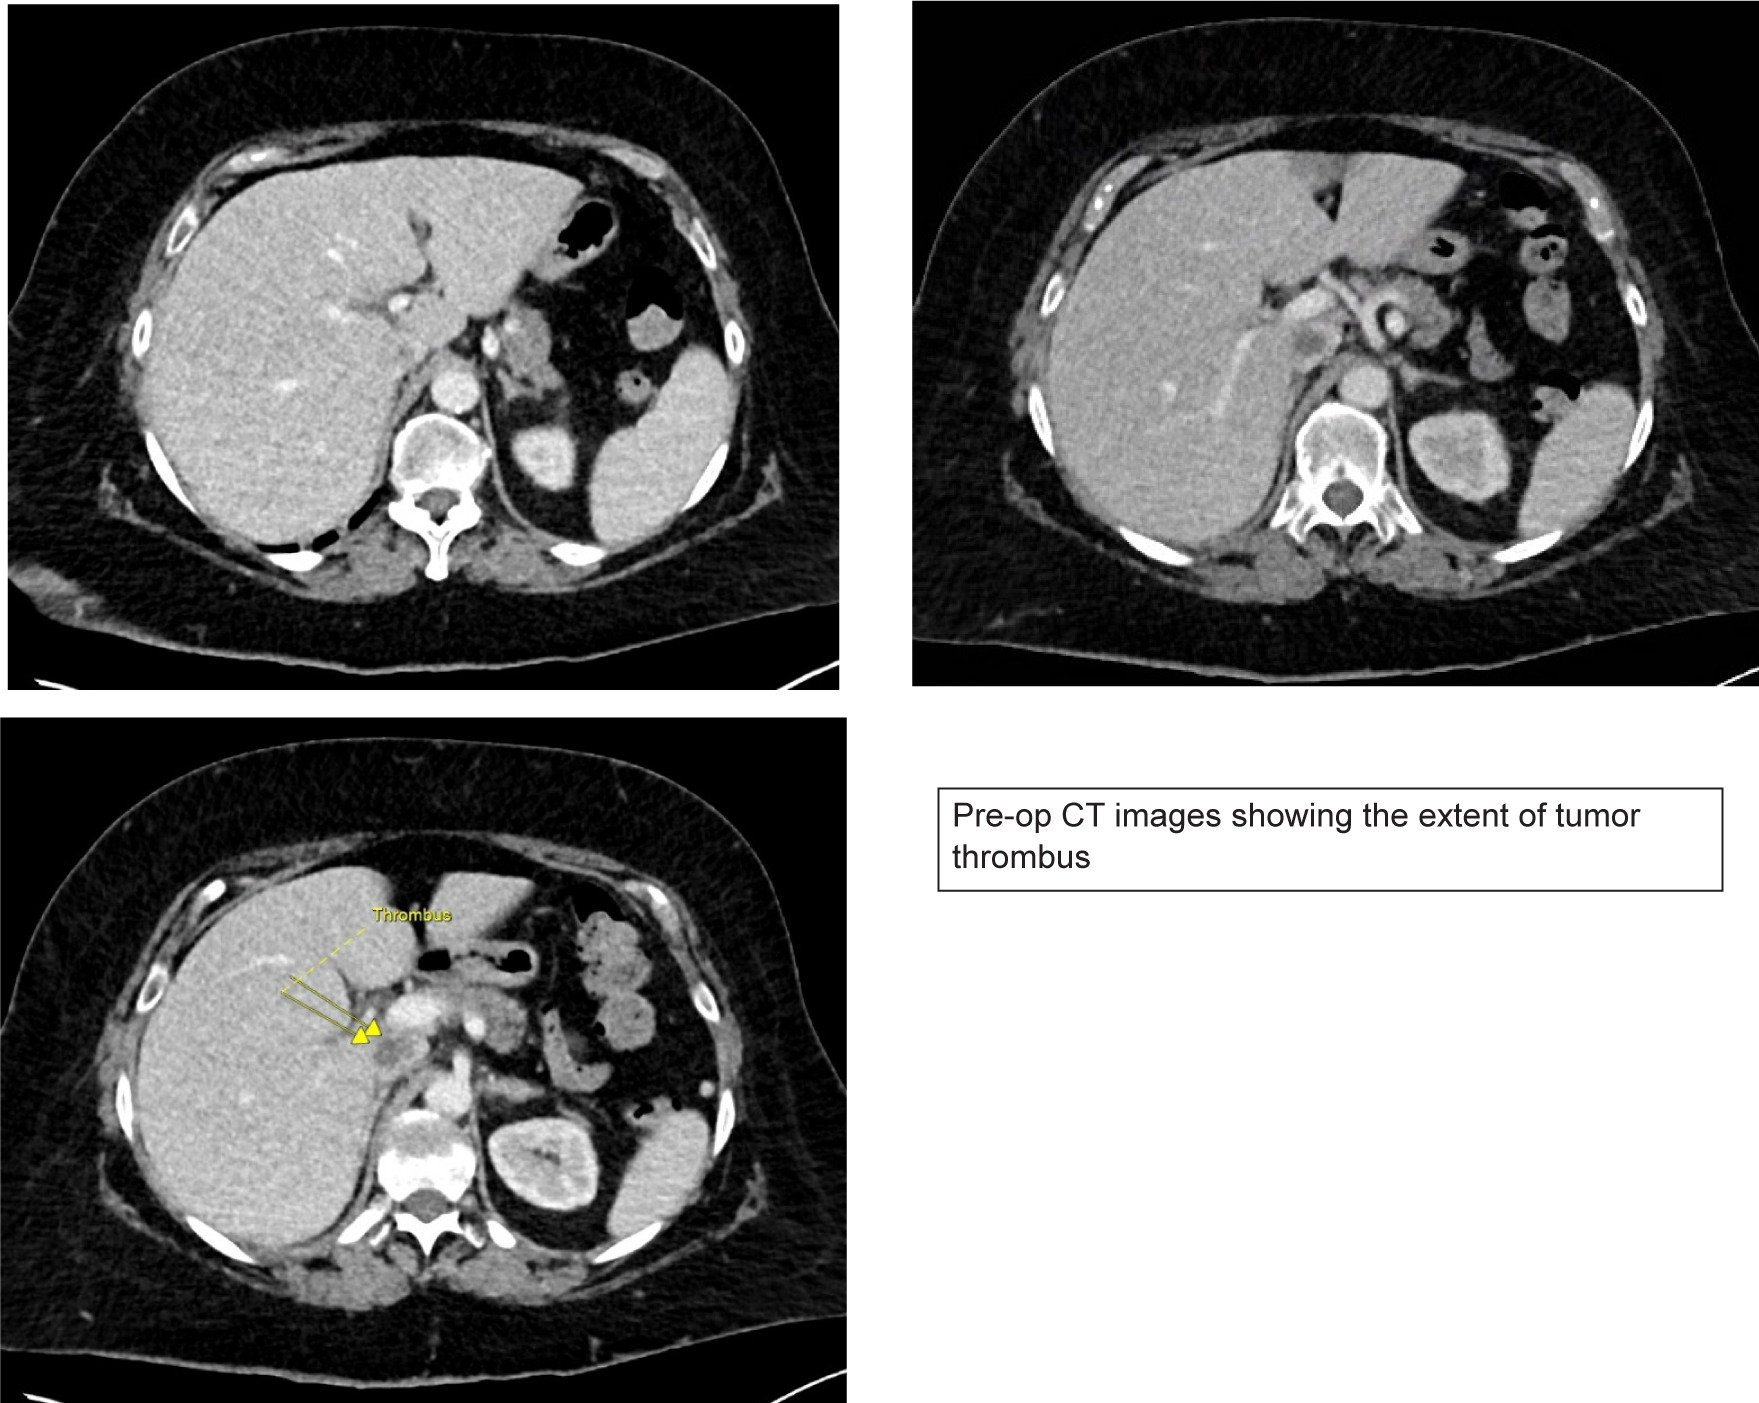

A 71-year-old female was assessed at our center for a new diagnosis of metastatic RCC. She presented to an outside hospital with hematuria and was found to have a 10 cm renal mass with tumor thrombus extending into the vena cava below the main hepatic veins (Mayo level II tumor thrombus) (Figure 1). Staging workup revealed multiple lung nodules up to 1.5 cm on CT which were biopsy proven to be metastatic clear cell RCC. Her medical history was notable for a pulmonary embolism (PE) diagnosed 9 months prior to presentation for which she completed a 6-month course of oral anticoagulation.

Figure 1: Pre-operative MRI showing tumor thrombus extending into the IVC below the major hepatic veins.